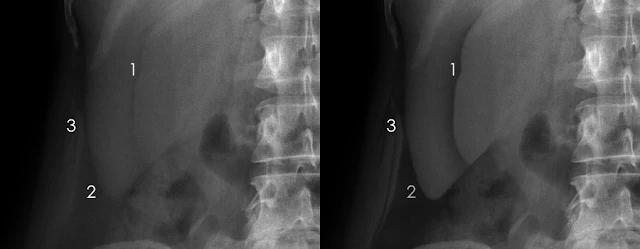

b.Hiện tượng Chilaiditi (Chilaiditi’s

phenomenon)

Ở những BN có gan nhỏ (xơ gan) hoặc cơ

hoành dẹt do phổi giãn quá mức (khí phế thủng) , tạo thành một khoảng trống ở

phần bụng dưới, trên gan. Khoảng trống đó có thể bị lắp đầy bởi ruột. Nếu ruột

chứa nhiều khí, sẽ tạo thành hình ảnh dễ nhầm lẫn với hơi tự do dưới cơ hoành.